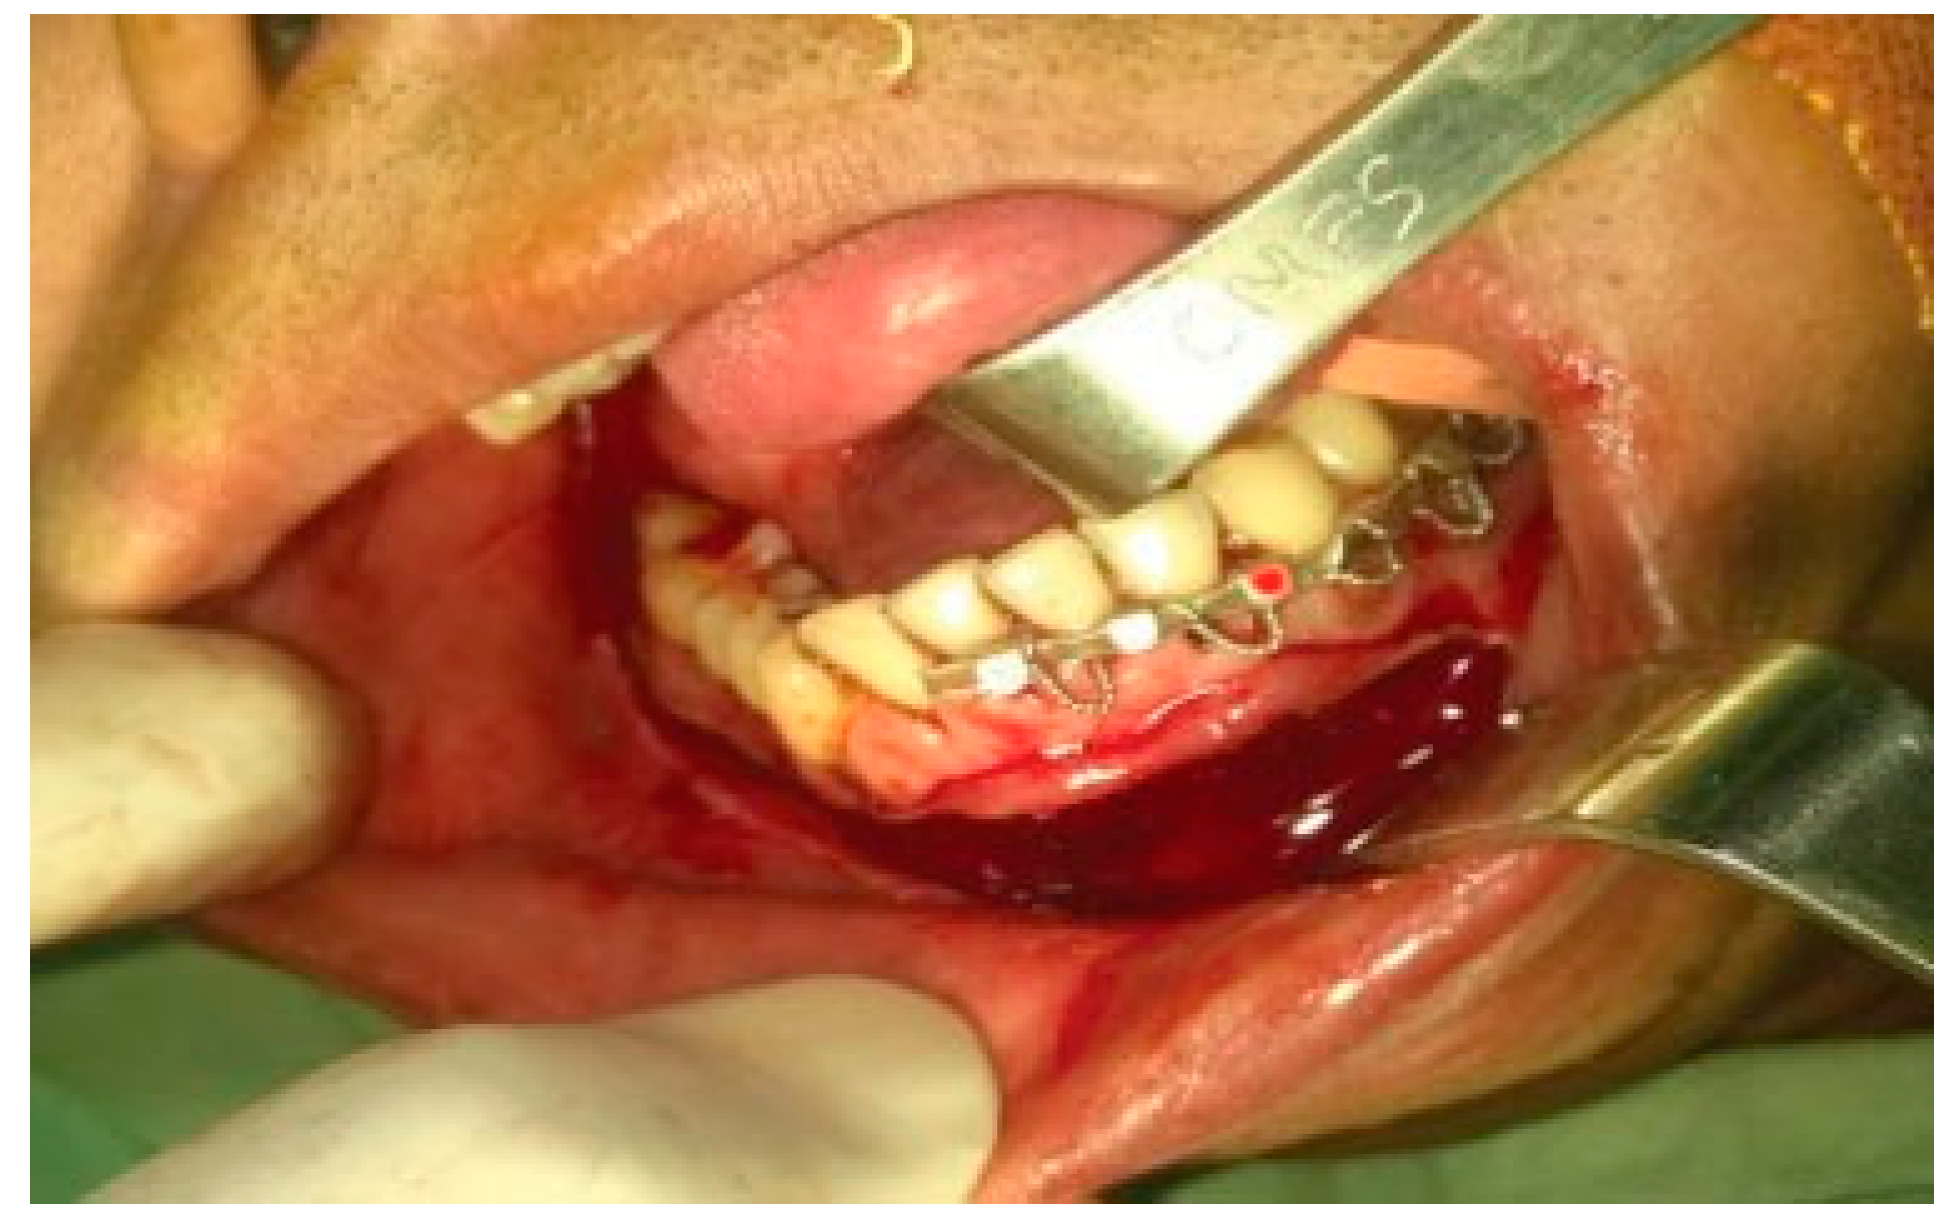

A transoral vestibular incision was given extending from left canine region to the entire right canine and body region of the mandible and extending upward along the anterior border of the ramus till the level of upper molars on the right side (Figure 4). Lateral aspect of the entire mandible was exposed till the ramus. Osteotomy was performed between the right lateral incisor and canine to fracture the mandible. The fractured mandible was swung laterally to expose the lingual side to facilitate subperiosteal exposure of the medial side of the fractured mandible (Figure 5). Posteriorly, the inferior alveolar neurovascular bundle was identified, clamped and ligated before severing it at its entry into the mandibular canal, progressing along the medial surface of ramus detaching the medial pterygoid muscle. A hole was then drilled onto the anterior aspect of fractured mandibular segment and a twisted wired was passed through to assist anterolateral traction for disarticulation (Figure 6). Under traction, the temporalis fibers were detached from the coronoid process and similarly the condyle was freed from capsular attachment to facilitate its disarticulation. The segment of the mandible along with the condylar and coronoid process on the right side till the fractured area was successfully removed transorally (Figure 7). The bleeders were identified and ligated and the wound was packed with wet gauge to arrest oozing of the blood from the adjacent soft tissues.

Figure 4. Transoral vestibular incision.